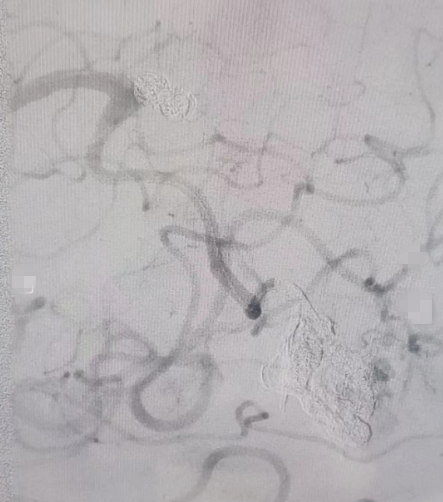

▲致密填塞的动脉瘤及动静脉畸形

手术由我科客座教授陈光忠亲自主刀,术中先使用弹簧圈单栓动脉瘤,然后将漂浮导管送至动静脉畸形瘘口,采用液态材料栓塞。Marathon微导管精准到位后使用兼容的弹簧圈小心填塞A4动脉瘤,达到致密栓塞。然后微导管继续朝远端超选,精准到位动静脉畸形巢,使用液体栓塞材料弥散栓塞,畸形巢内动脉瘤被胶水填充后不再显影。因已达到止血治疗目的,按计划决定不再予更改通路栓塞其他供血动脉。术后患者无不适,恢复迅速,目前已顺利出院。